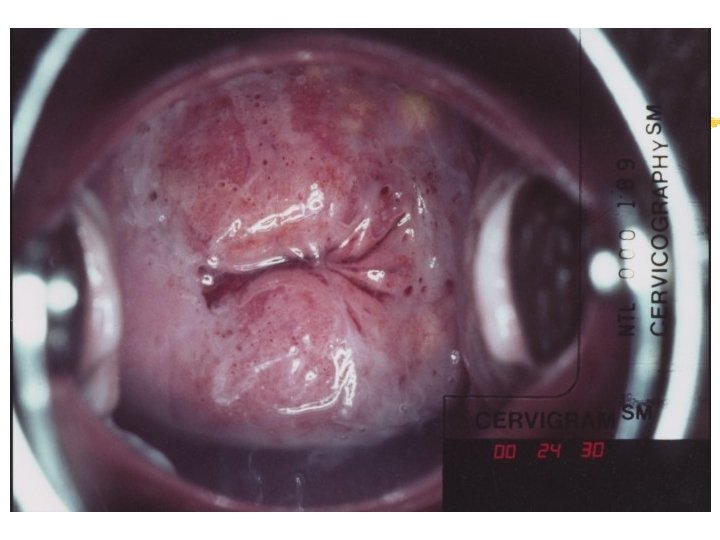

Cervicography: This is NOT Colposcopy High-quality colposcopic-type photography of the cervix Cervicoscope - Hand-held camera with a macrolens and a ring-flash Cervicogram - 35 -mm photo slide is taken Principles Recognition of lesions by means suitable magnification and illumination Fix up the problems of colposcopy 1. a less expensive form 2. noninvasive method 3. do not require expert skill

Procedures of cervicography A) Taking a 35 -mm cervicogram (1) Insert speculum and open as wide as possible … expose an entire cervix and upper vagina (2) Apply first application of 5% acetic acid by dabbing … cleanse the cervix of blood and mucus (3) View the cervix through the cervicoscope … allows time to begin taking epithelial change (4) Apply second application of acetic acid. (5) Take two cervicogram pictures B) Developing the images C) Interpreting a magnified image that was projected on the screen (1) Negative if no definitive lesions are visible (2) Atypical if there was evidence of acetowhite lesion of doubtful significance (3) Positive if there was evidence of a minor or major-grade lesion or cancer